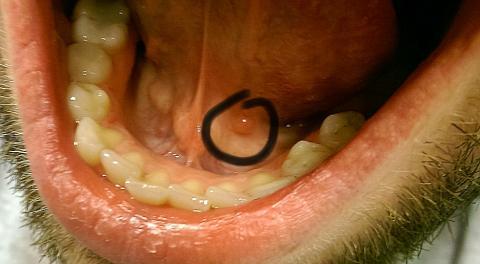

Dobrý deň. Už dlhšiu dobu (asi rok) pozorujem pod jazykom červenú hrčku o veľkosti asi 5mm. Nebolí ma a ani sa nezväčšuje. Prikladám aj fotografiu. Viete mi prosím povedať o čo by sa mohlo jednať ? Ďakujem.

Dobrý den, jde o cystu (tzv. mukokélu), která vznikla ucpáním vývodu malé slinné žlázky v dutině ústní. Ve většině případů zmizí sama, pokud začne dělat obtíže (růst, bolet), navštivte lékaře (stomatolog nebo ORL).